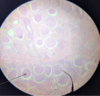

Toxoplasma - Tachyzoites

Stained with immunofluorescent method

Toxoplasma

Tachyzoites

Toxoplasma Gondii

Tachyzoites

Giemsa staining